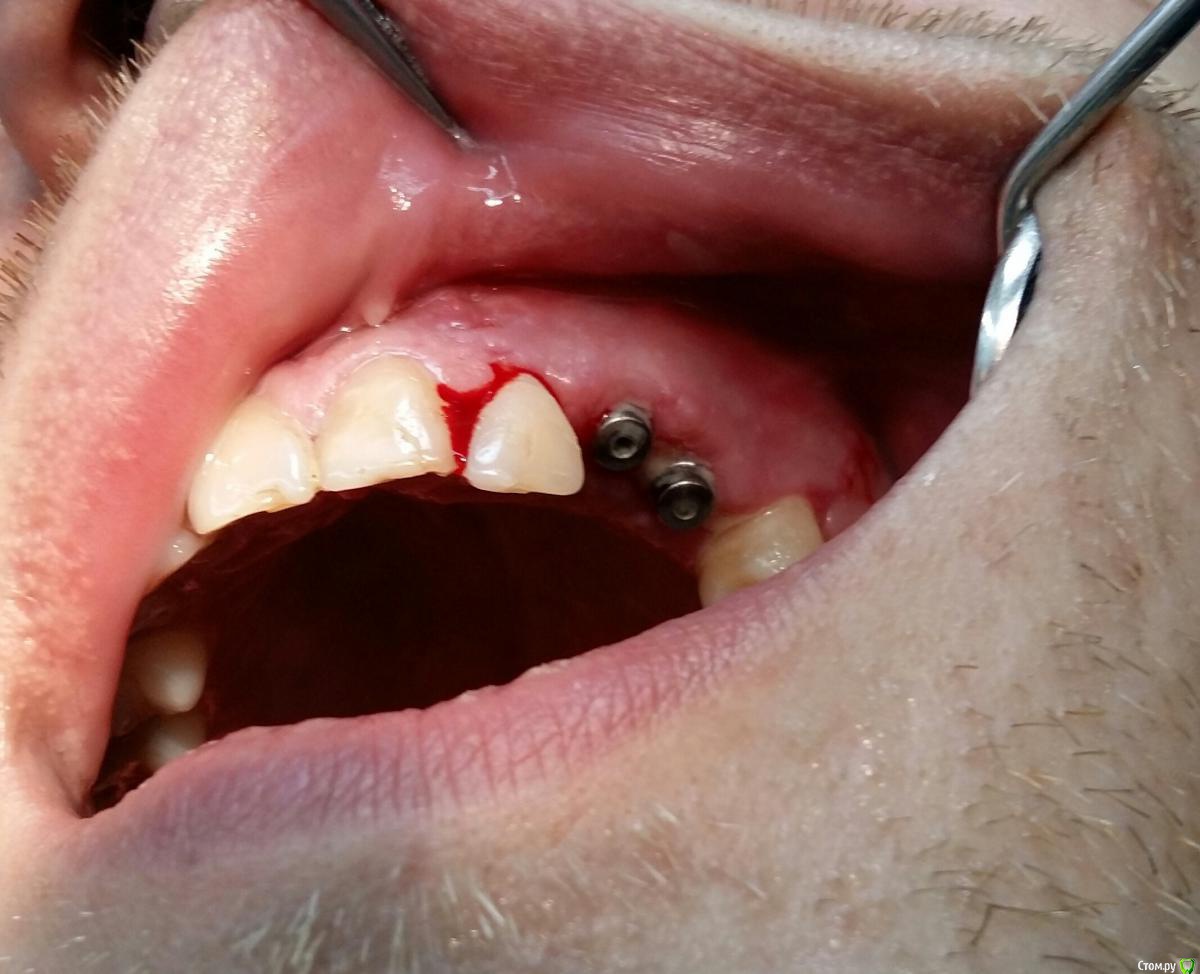

Kostoprav Опубликовано 26 марта, 2017 Поделиться Опубликовано 26 марта, 2017 (изменено) извините за качество фотографт: ауто + биопласт крошка, мембрана еволюшендырка возле 22-ревизия периапикального процесса Изменено 26 марта, 2017 пользователем Kostoprav 3 Ссылка на комментарий

Dman Опубликовано 27 марта, 2017 Поделиться Опубликовано 27 марта, 2017 Почему приняли решение ушивать с формирователями а не наглухо? Ссылка на комментарий

Kostoprav Опубликовано 27 марта, 2017 Автор Поделиться Опубликовано 27 марта, 2017 Почему приняли решение ушивать с формирователями а не наглухо?использовал фдм что бы не пиниться с небной стороны Ссылка на комментарий